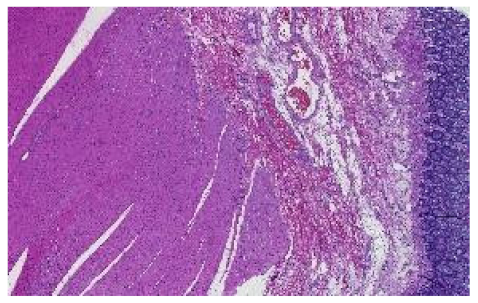

The preprocessing stage began with 66 WSI scans; we digitally cropped one region of interest (ROI) of size 1440 × 904 pixels for each tissue type in each slide. This resulted in three sets of images of 66 ROIs each, one set for the kidney, one for the skin, and one for the colon tissue. Cropping was used to minimize the presence of the non-tissue-related background, such as dust, hair, fibers, and other artifacts from previous preprocessing steps. The selected region coordinates were approximately the same within each tissue type. Each ROI was localized to cover an approximately sufficient area in each tissue type. Figure 3 shows samples of such ROIs for each tissue type amongst nine randomly chosen laboratories (three laboratories per tissue type).

Figure 3.

For illustration purposes, three ROIs from three laboratories per tissue type (column-wise). The first column is skin, the second column is kidney, and the last column is colon.